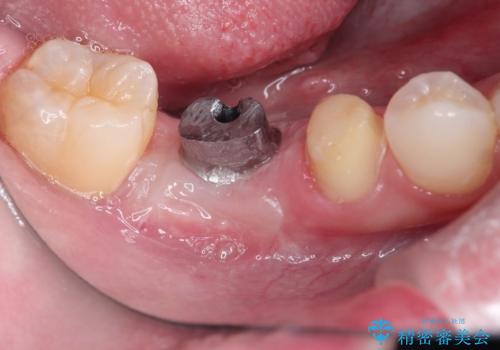

保存不可能な歯を抜歯してインプラント治療

- 右下の奥歯の調子がよくないとのことで来院されました。

レントゲン・口腔内診査をお行い、保存が難しいことがわかりました。

抜歯後インプラントをする計画としました。